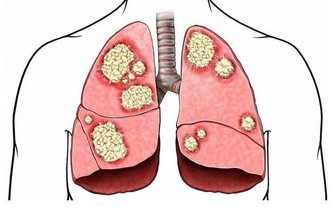

香菜含有大量的胡蘿蔔素,能夠有效保護眼、呼吸道、泌尿道及胃腸道黏膜,防止細菌和病毒的感染,從而提高人體的免疫能力。

香菜中含有的黃酮類、多種維生素和微量元素等物質,具有抗癌、護腎、降血糖等作用。